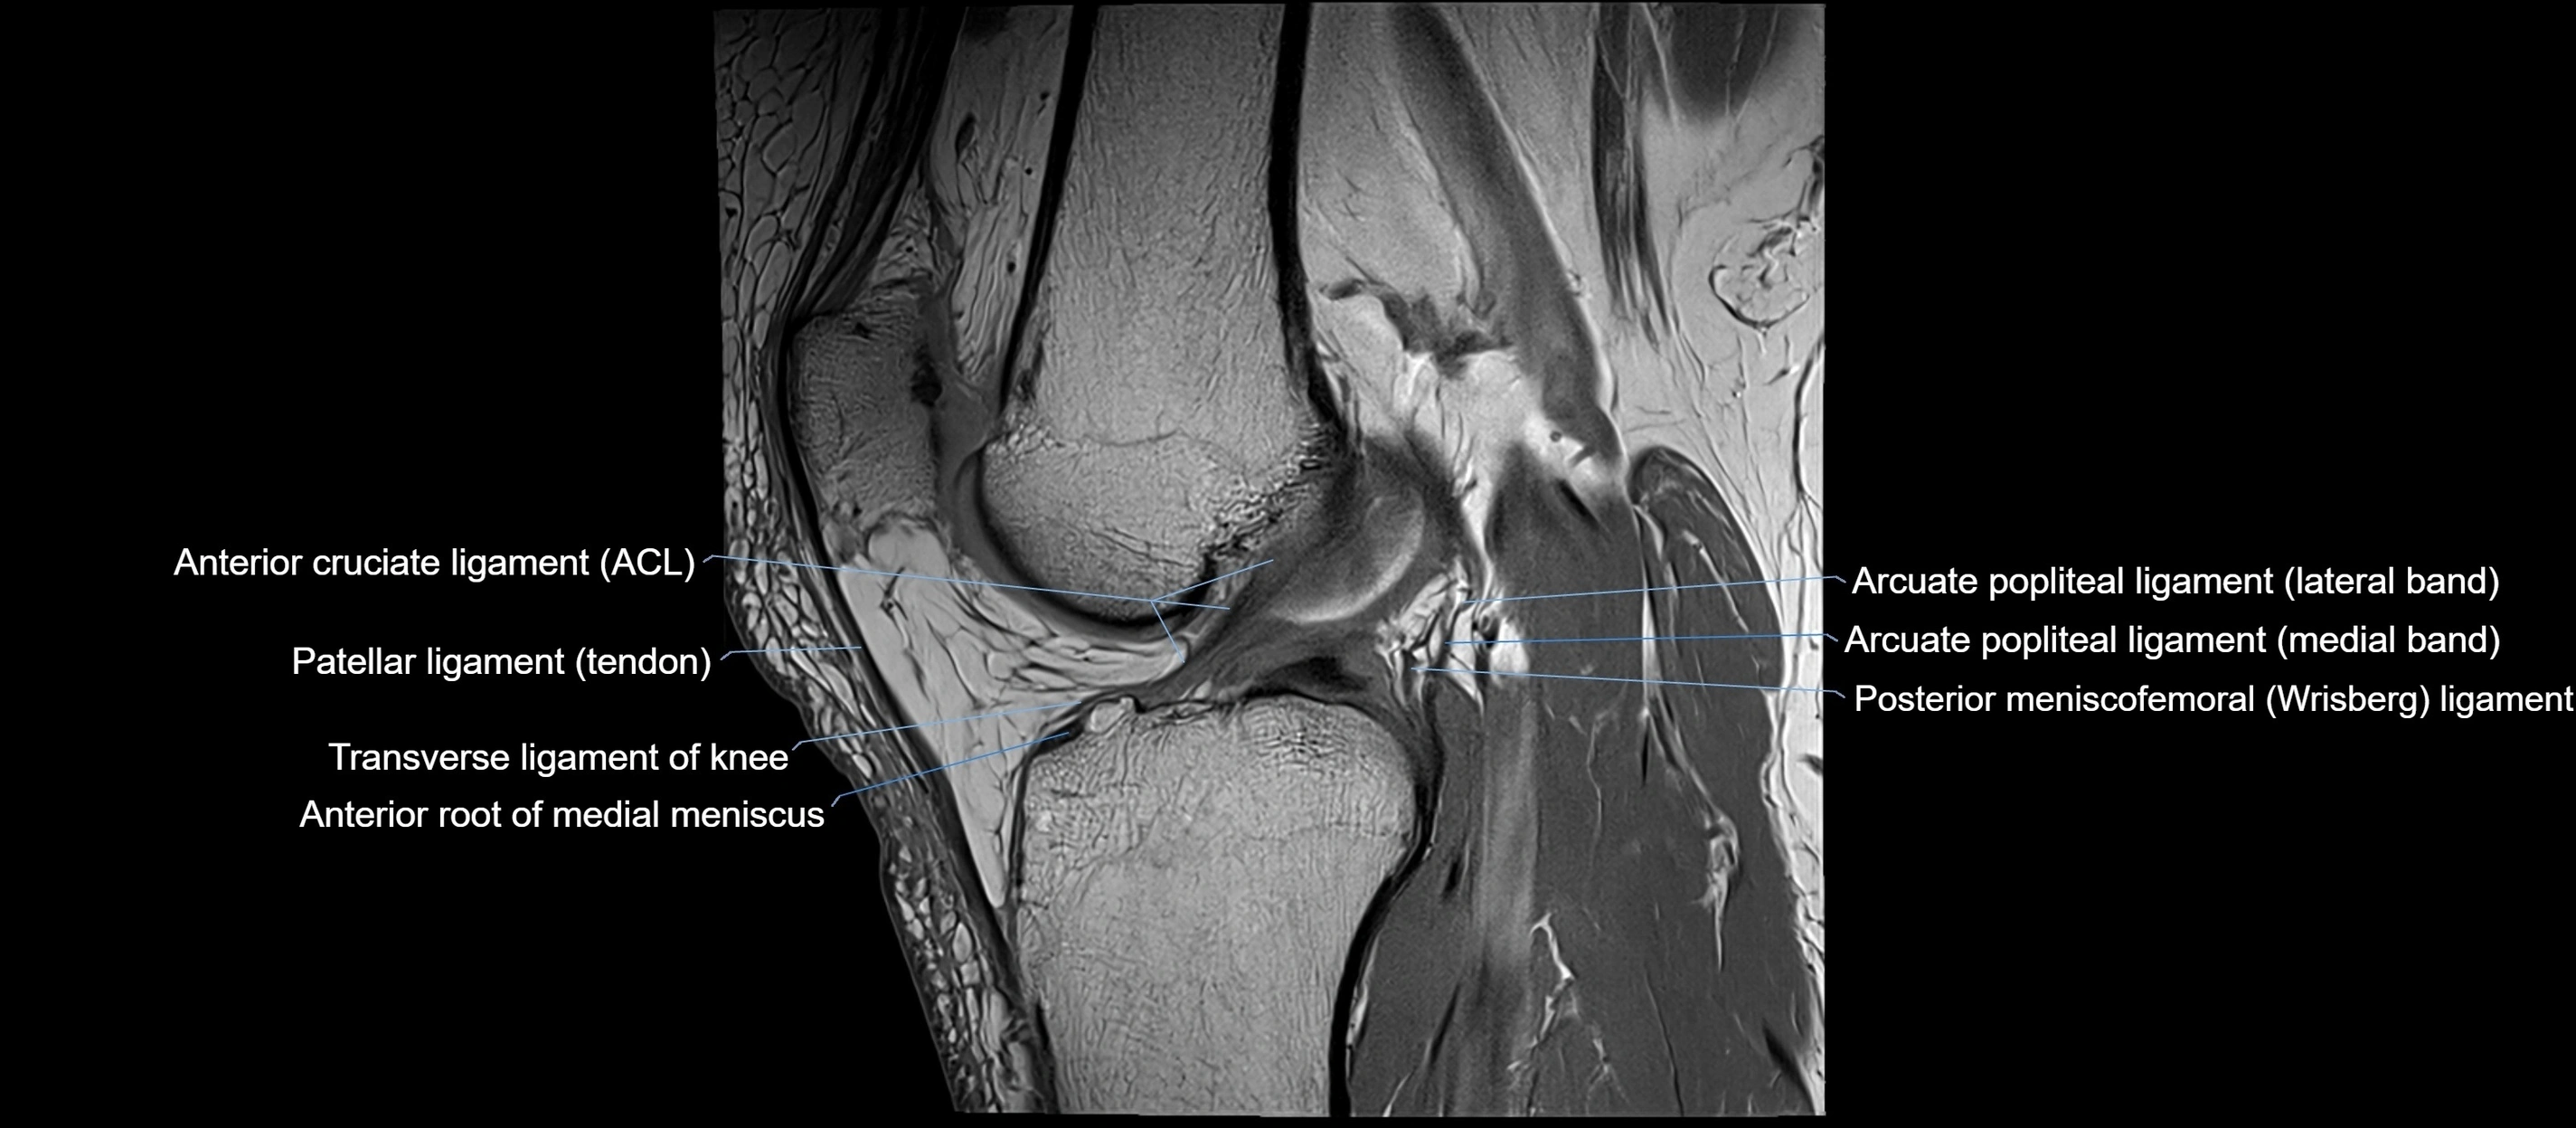

MRI Appearance

T1-weighted images:

• Normal ACL appears as a low-signal band-like structure crossing the intercondylar notch

• Surrounded by intermediate signal synovial fluid and fat planes

T2-weighted images:

• Normal ACL remains low signal

• Partial or complete tears appear as discontinuity, increased signal, or fiber laxity

MRI images

image